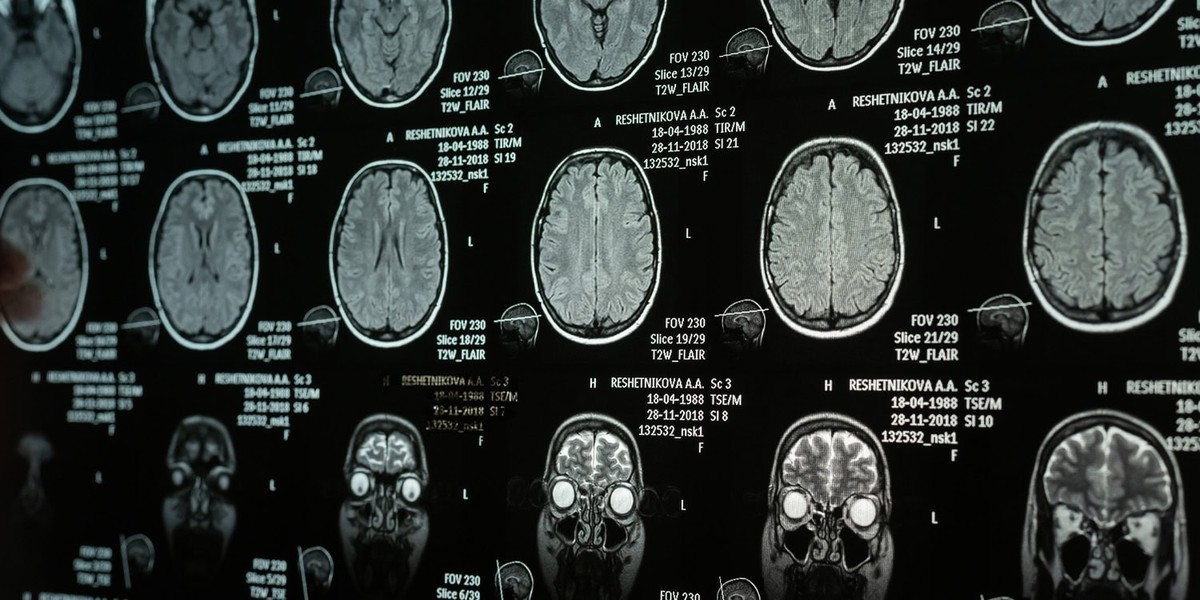

تصویر زیر نشان دهنده ابعاد مختلف تغییرات ساختاری در نواحی حساس سیستم عصبی است که بر اثر الگوهای خواب نامناسب در سنین بلوغ ایجاد می شود.

در کنار داده های خواب، محقق ها اسکن های MRI تمام شرکت کننده ها رو هم بررسی کردن. اونا به اسکن های ساختاری نگاه کردن که اندازه فیزیکی، حجم و ضخامت مناطق خاصی از مغز رو نشون می ده.

اونا همچنین اسکن های عملکردی حالت استراحت رو بررسی کردن که جریان خون رو توی مغز موقعی که فرد آروم دراز کشیده اندازه می گیره. این اسکن های عملکردی به محقق ها اجازه می ده تا شبکه های مغزی رو نقشه برداری کنن.